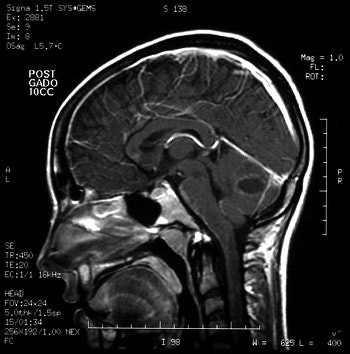

"As the popularity of body art grows, frequency and spectrum of piercing-site infections may increase. Physicians need to consider piercing sites as a source for potential distant infections," wrote Martinello and Cooney in an abstract for the 2001 Infectious Diseases Society of America conference. Images courtesy of Dr Richard Martinello.

However, a brain CT scan revealed a "right cerebellar enhancing lesion with surrounding edema, and an MRI scan with gadolinium confirmed the presence of a solitary brain abscess," the authors reported. The patient underwent a right suboccipital craniotomy to drain the abscess and was then treated with antibiotics. A follow-up CT showed complete resolution of the abscess.

"A cerebellar abscess occurring secondary to a tongue infection would presumably result from hematogenous spread, because the venous drainage of the tongue flows from the lingual vein into the internal jugular vein," they explained.